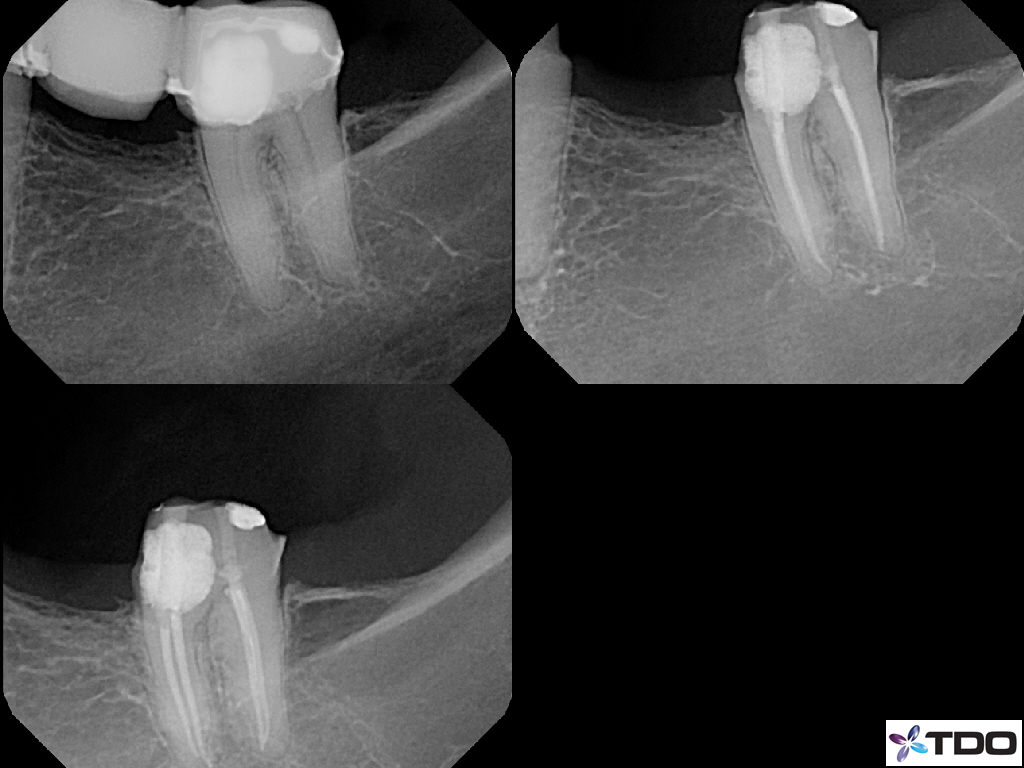

These cases show a level of commitment to conservative endodontics rarely seen in endo today. Plus the restorative excellence is inspiring and should stimulate all endodontists to up their game and help others realize how important the restorative aspect of endodontics is.